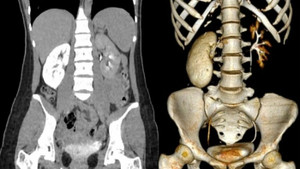

Ung thư thận là một trong những loại ung thư phổ biến ở nam giới Việt Nam. (Ảnh minh hoạ)